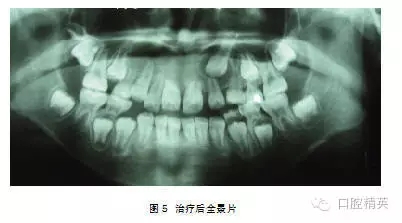

典型病例2:患者,女,10歲,因1|未萌來我院就診(圖1)。

檢查:1|未萌, |1全萌, 2|1之間間隙為5mm。X線示:1| 骨內(nèi)埋伏,倒置,牙冠的舌側(cè)向外,彎根。 |1牙根已形成。(圖2、3)。

處理:2004年3月行外科開窗+正畸牽引治療,7個(gè)月后檢查:1|已萌出,未完全到位,1|唇側(cè)牙根處稍隆起,即為彎曲的牙根。因1|為彎根比較嚴(yán)重,如完全排齊有可能使牙根暴露,故未完全排齊(圖4、5)。